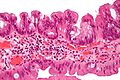

Investigadores del Servicio de Digestivo del Hospital del Mar, del IMIM (Instituto de Investigación del Hospital del Mar) y del CREAL (Centro de Investigación en Epidemiología Ambiental), junto con el Servicio de Gastroenterología del Hospital Clínico de Barcelona y el Instituto de Investigaciones Biomédicas August Pi i Sunyer (IDIBAPS), han liderado un estudio que identifica la correlación entre variantes genéticas de susceptibilidad y las diferentes características clínicas y familiares de pacientes afectados de cáncer colorectal. Este estudio, realizado dentro del marco del proyecto EPICOLON -iniciativa de la Asociación Española de Gastroenterología- y del CIBER de Enfermedades Hepáticas y Digestivas (CIBERehd), acaba de ser publicado en la revista Gastroenterology, líder de la especialidad. Se trata de un multicéntrico de base poblacional que recogió todos los pacientes con Cáncer Colorectal (CCR) en 25 hospitales de España. Los resultados podrían contribuir a mejorar la detección del Cáncer Colorectal Familiar gracias a la identificación de personas con mayor susceptibilidad a desarrollar este tipo de tumor.

El cáncer colorectal es una de las neoplasias más frecuentes en los países occidentales, siendo la segunda causa de muerte por cáncer en nuestro país. Los factores genéticos y ambientales juegan un papel fundamental en su desarrollo. La susceptibilidad heredada es responsable de aproximadamente el 30% del total de casos de CCR. El cáncer colorectal hereditario explica menos del 5% de los casos y el resto de predisposición heredada podría ser atribuida a la combinación de un gran número de polimorfismos o SNPs (cambios de un solo nucleótido en la cadena de ADN). Estos SNPs son comunes y de baja penetrancia, es decir, por sí mismos confieren al individuo una baja probabilidad de sufrir la enfermedad. Eso sí, en función de su número y asociados a otros factores, pueden aumentar el riesgo de desarrollarla.